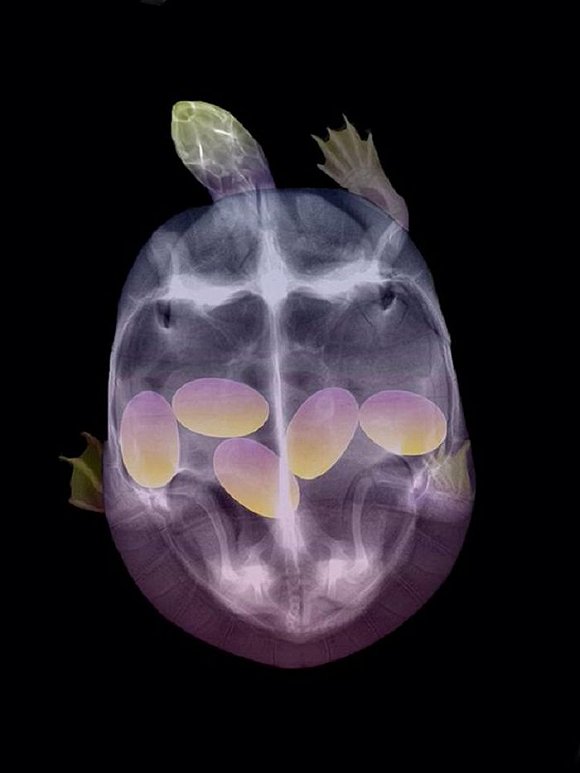

可爱又毛骨悚然 怀孕动物的X光片

人类之间分享母亲肚子里胎儿的X光片是一件非常常见的事情,但是,纵使你觉得自己对X光片已经见怪不怪,在看到了下面这些怀孕动物的X光片后你仍旧会说"哦我的天哪"。

以下就是一些动物在怀孕时的X光片。

1. 乌龟